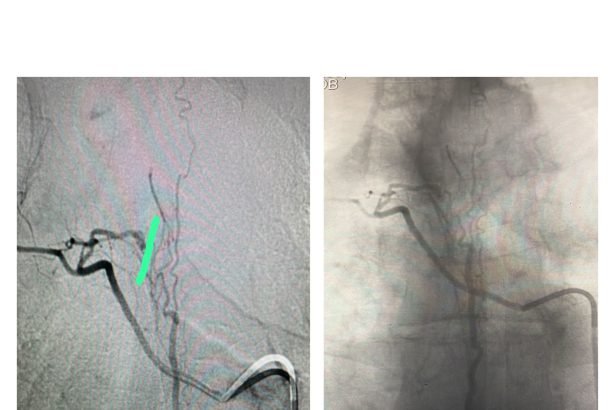

تمكّن الفريق الطبي في وحدة القسطرة بالمستشفى التخصصي، بقيادة الدكتور حازم حبوب استشاري الاشعة التداخلية، من إجراء تداخل طبي متقدم لمعالجة حالة شلل طرفي ناتج عن وجود تشوه شرياني وريدي في النخاع الشوكي، وذلك تحت المراقبة الفسيولوجية العصبية الدقيقة.

وتمت العملية بنجاح من خلال استحضار الإمكانيات الحسية والحركية للمريض أثناء الإجراء، لتفادي أي مضاعفات محتملة.

ويُعد هذا التدخل الأول من نوعه الذي يُنفذ في وحدة القسطرة بالمستشفى، مما يعكس التقدم المستمر في مستوى الرعاية الطبية والتخصصية المقدّمة.

ومن الجدير بالذكر أن قسم القسطرة في المستشفى التخصصي يضم أحدث الأجهزة ومنها Philips Azurion 7 Flexarm الأحدث بالعالم والأول في الشرق الأوسط وجهازGE Innova الأول من نوعه في الأردن.